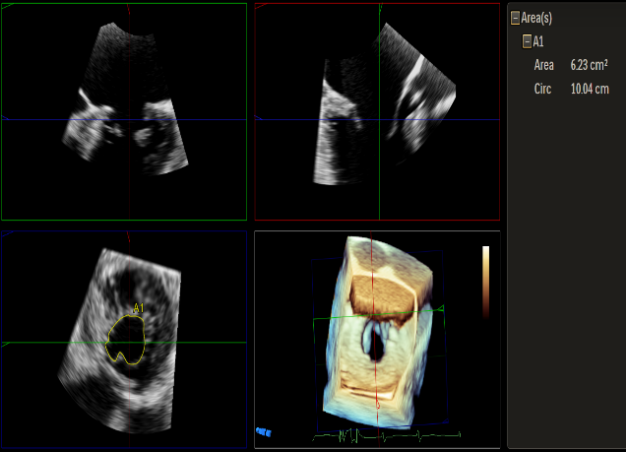

Qlab软件勾画估测瓣口面积约:6.23cm²